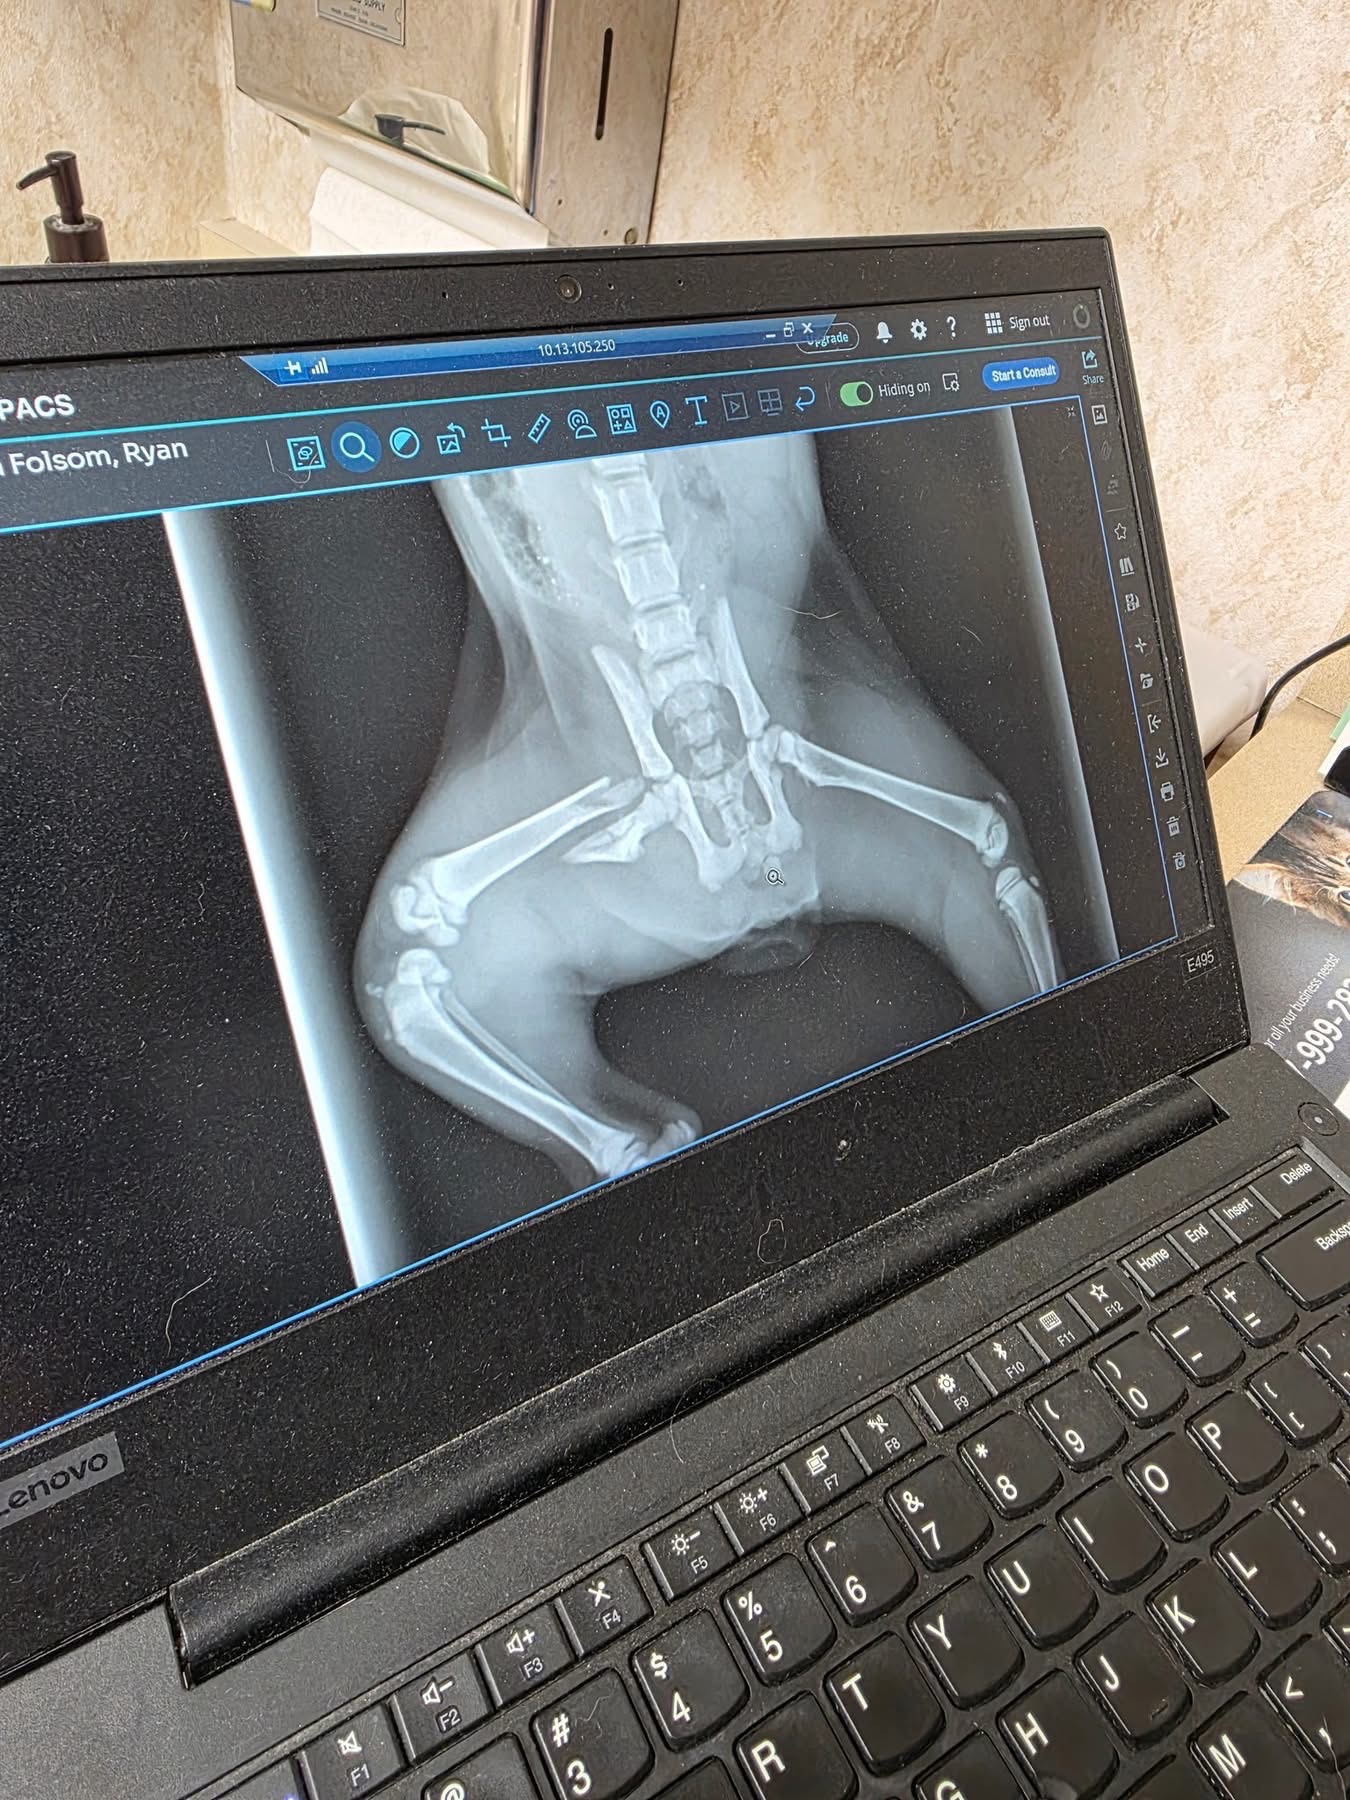

We were driving down 61st and Lewis when Ryan stopped in traffic to save this kitty. She was laying in the middle of the road, unable to move. We rushed her to the vet and found out she has a broken leg that will need to be amputated.

As most of you know, we love to rescue, and we will be taking this kitty home to give her a good life. We’re putting this out here to see if anyone could help contribute to her surgery she will be having Monday. Thank you for reading.